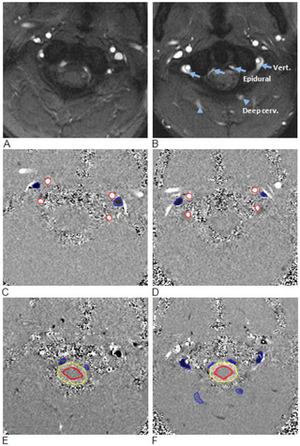

- 3.26 Panorama Ultrasound for Navigation and Guidance of Epidural Anesthesia